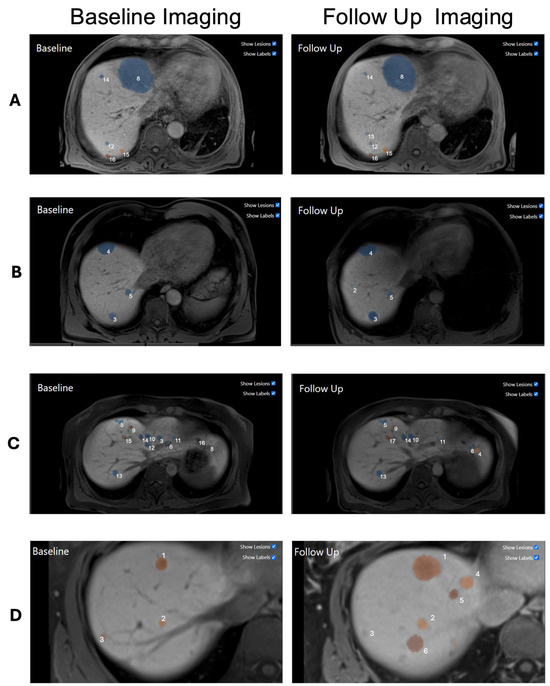

2.2. Automatic Lesion Detection and 3D Tracking

2.3. Evaluation Study

| Progressive | The diameter increased by at least 20% |

| Stable | The diameter change is between 20% increase and 30% decrease |

| Regressive | The diameter decreased by at least 30% |

| New | The lesion only appears in the follow-up MRI |

| Merged | The lesion grew together with another lesion |

| Too small to measure | The lesion has a diameter smaller than 5 mm at both timepoints |